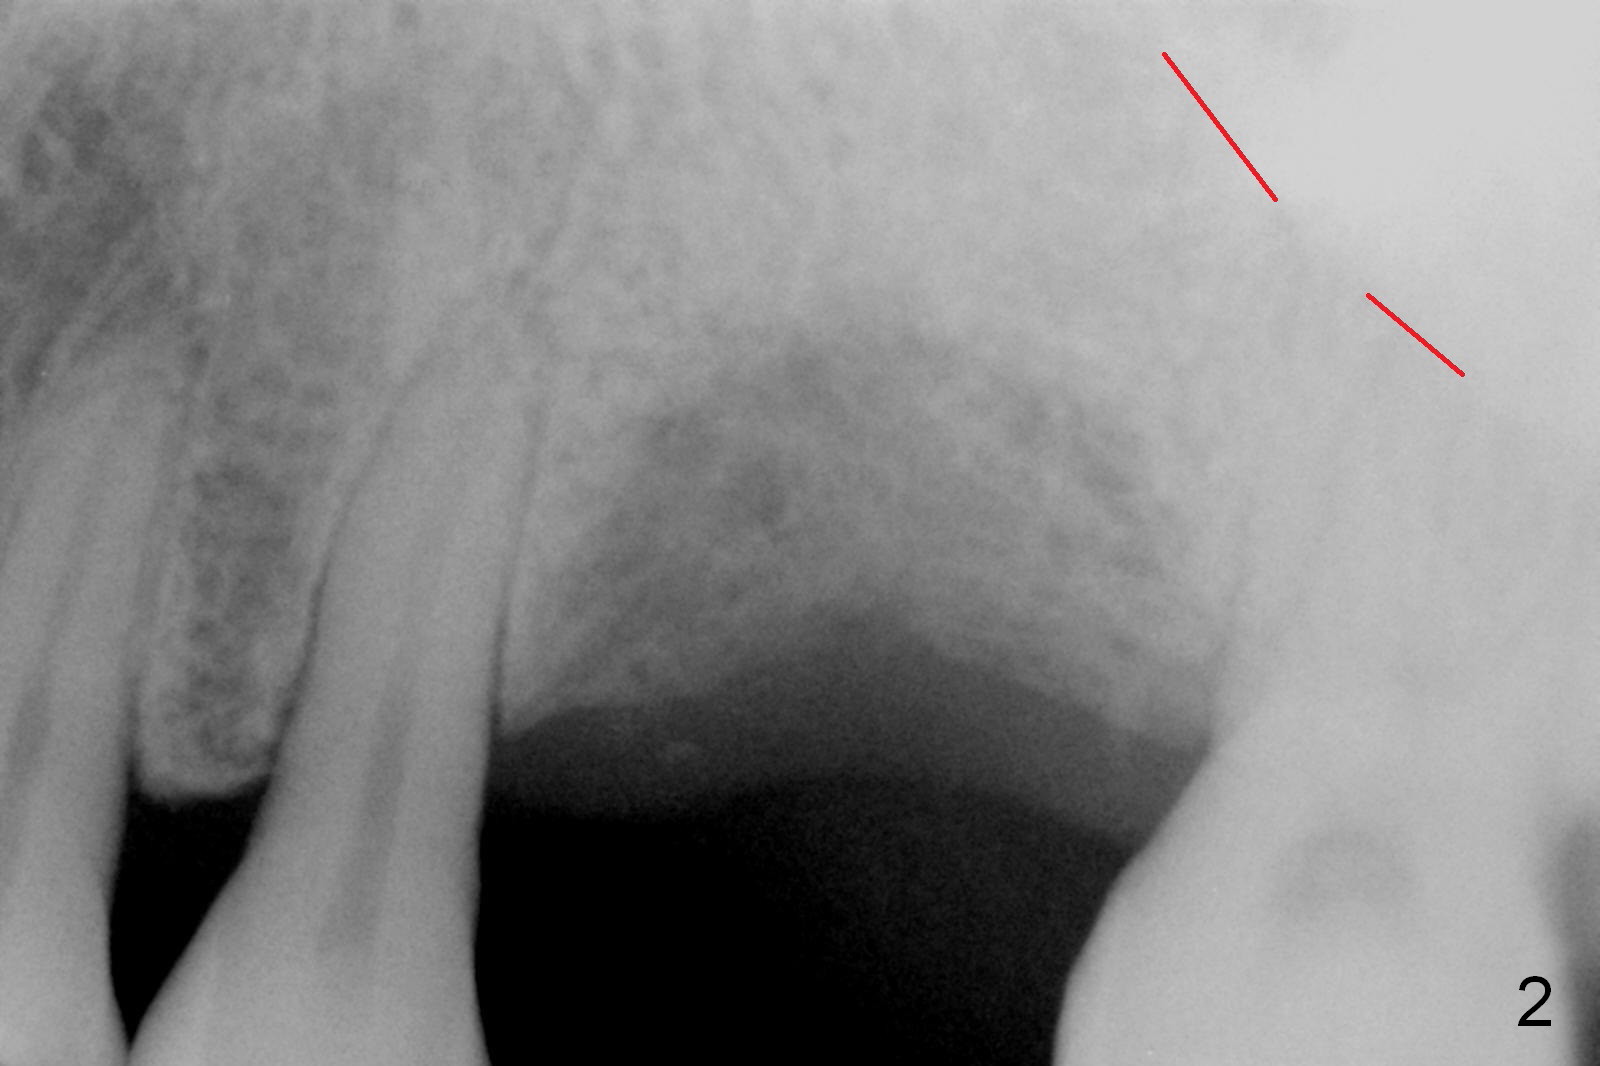

The tooth #14 of a 52-year-old lady had severe bone resorption 6 years ago (Fig.1 (red dashed line: sinus floor)). The bone resorption persists after the tooth exfoliated (Fig.2). Clinically, the buccal plate (Fig.4 (occlusal view) upper panel: B) is concave (take preop photos). #15 scalpel will be used for incision (red line in Fig.4 lower panel, near the lingual plate (L)) and initiation of bone expansion. The latter is followed by bone scalpels, bone blades and RTs at the depth of 14 mm. A 4.5x17 mm Tatum tapered tap is used for 14 mm. PA is taken. If the bone is dense, the depth is less than 14 mm in bone. Use RT2,3 to reach 17 mm. A 5x14 mm bone-level implant is placed (Fig.3). Crown cementation will be done for the tooth #3 before surgery.